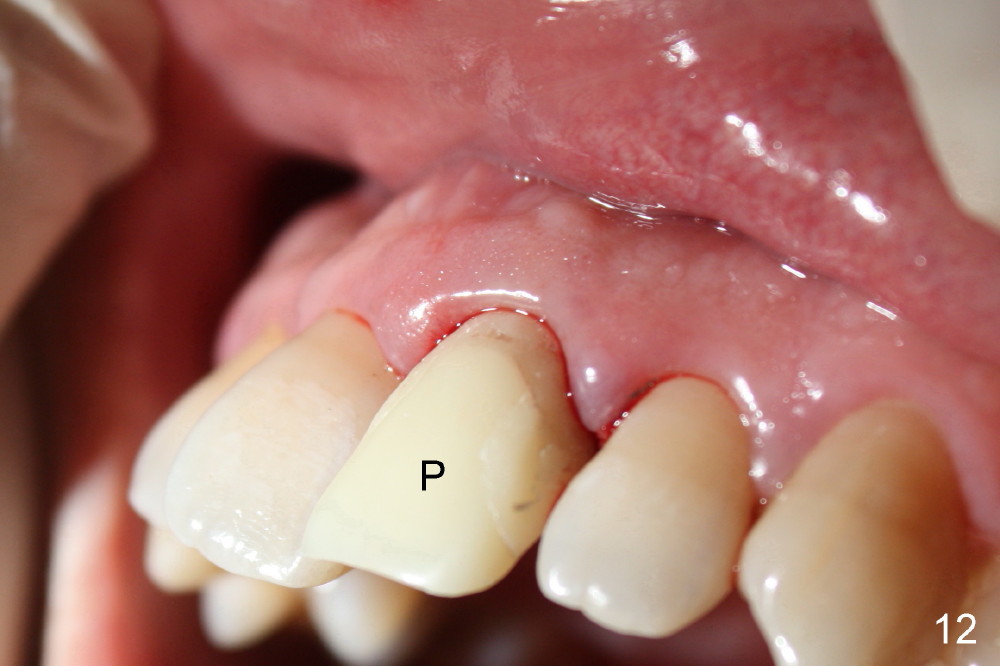

Bone expansion allows the implant (Fig.9 I) to have primary stability (insertion torque between 50 and 60 Ncm), since the cortex of the incisive canal is apparently intact. Allograft is placed in the labial gap (Fig.10, 11 *) following installation of the abutment (A). Finally an immediate provisional (Fig.10,12 P) is cemented. Fig.13,14 are taken 8 days postop. The patient returns 3 months postop (Fig.15,16). Osteointegration appears to have occurred (Fig.15 arrowheads) and is more obvious 9 months postop (Fig.17).